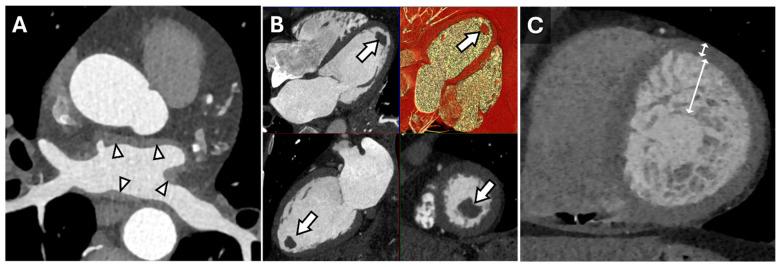

心脏CT在心肌病表型分析中的应用

心脏计算机断层扫描(CT)发展迅速,已成为诊断和预测各种心血管疾病的重要工具。虽然超声心动图和心脏磁共振成像(CMR)仍是心肌评估的金标准,但现代CT技术提供了更高的空间分辨率,使其成为临床实践中的重要工具。心脏CT的应用范围已超越冠状动脉疾病评估,目前在心肌病和结构性心脏病的评估中发挥着关键作用。光子计数CT等创新技术能够精确估计心肌细胞外容积,有助于检测浸润性疾病和心肌纤维化。此外,基于CT的心肌应变分析可对心肌收缩功能受损进行分类,而在心肌病评估中,量化心脏容积和功能仍然至关重要。本综述探讨了心脏CT在心肌病表型分析中的新兴作用,重点介绍了近期的技术进展。